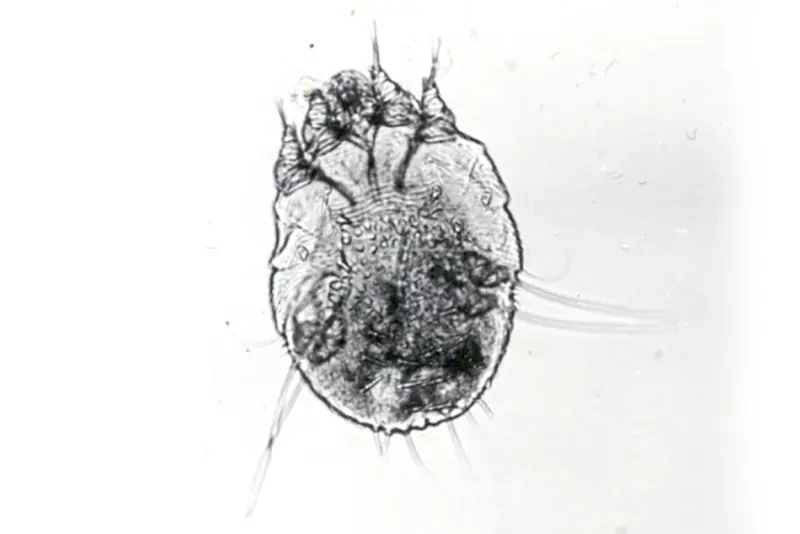

Skabbmidden (Sarcoptes scabiei var. hominis) er bare 0,3-0,5 mm lang, og knapt synlig med det blotte øyet. Hunnmidden graver overfladiske ganger i huden hvor den daglig legger 2-3 egg som klekkes som larver etter 3-4 døgn. Larvene trenger ytterligere 3-4 dager på å utvikle seg til nymfer. Midden gjennomgår to nymfestadier (den bruker 2-3 dager for hvert stadium) før den utvikler seg til voksen midd. Det er imidlertid beskrevet store variasjoner i utviklingstid fra egg til voksen midd; fra 7 til 21 dager (1-5). En person har sjelden mer enn 5-15 hunnmidd.